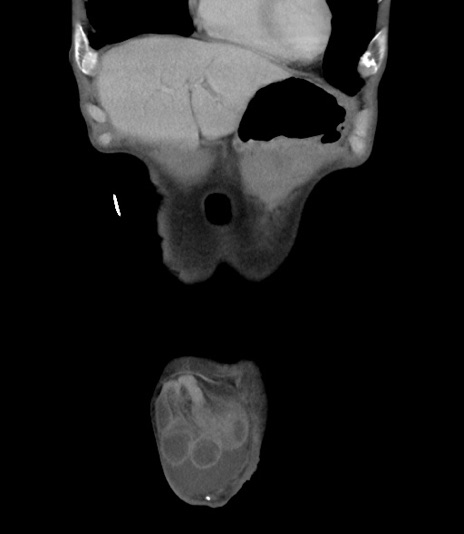

症例3(冠状断像)

【症例】 70歳代男性

【主訴】右鼠径部腫瘤、疼痛

【現病歴】本日朝より上記主訴あり、受診。

【既往歴】膀胱癌にて膀胱全摘、両側尿管皮膚瘻

【データ】WBC 5600、CRP 0.56